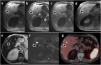

The use of hepatobiliary-specific contrast agents in liver MRI is a crucial diagnostic tool for evaluating liver disease, enabling the detection and characterisation of focal lesions and vascular alterations, as well as the assessment and grading of chronic hepatopathy. Paramagnetic hepatobiliary-specific contrast agents are gadolinium-based, partially taken up by hepatocytes, and excreted via both renal and biliary pathways. There are two linear ionic molecules that are currently commercially available: gadobenic acid (Gd-BOPTA) and gadoxetic acid (Gd-EOB-DTPA). Their main clinical indications include distinguishing and characterising focal liver lesions on healthy liver tissue, diagnosing and staging hepatocellular carcinoma in patients with chronic hepatopathy, and increasing reliability in the detection of hepatic metastases in oncology patients, especially prior to surgery. They are also useful in the evaluation of the biliary tract and in assessing complications of hepatic surgery such as bile leaks.